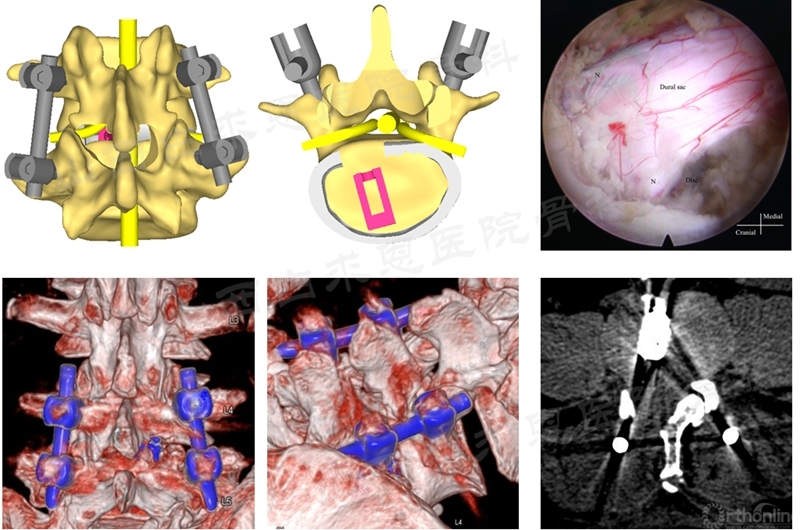

1. 经关节突入路PE-PLIF技术要点

N:Nerve root(神经根);Disc(椎间盘)

(7)病例分享